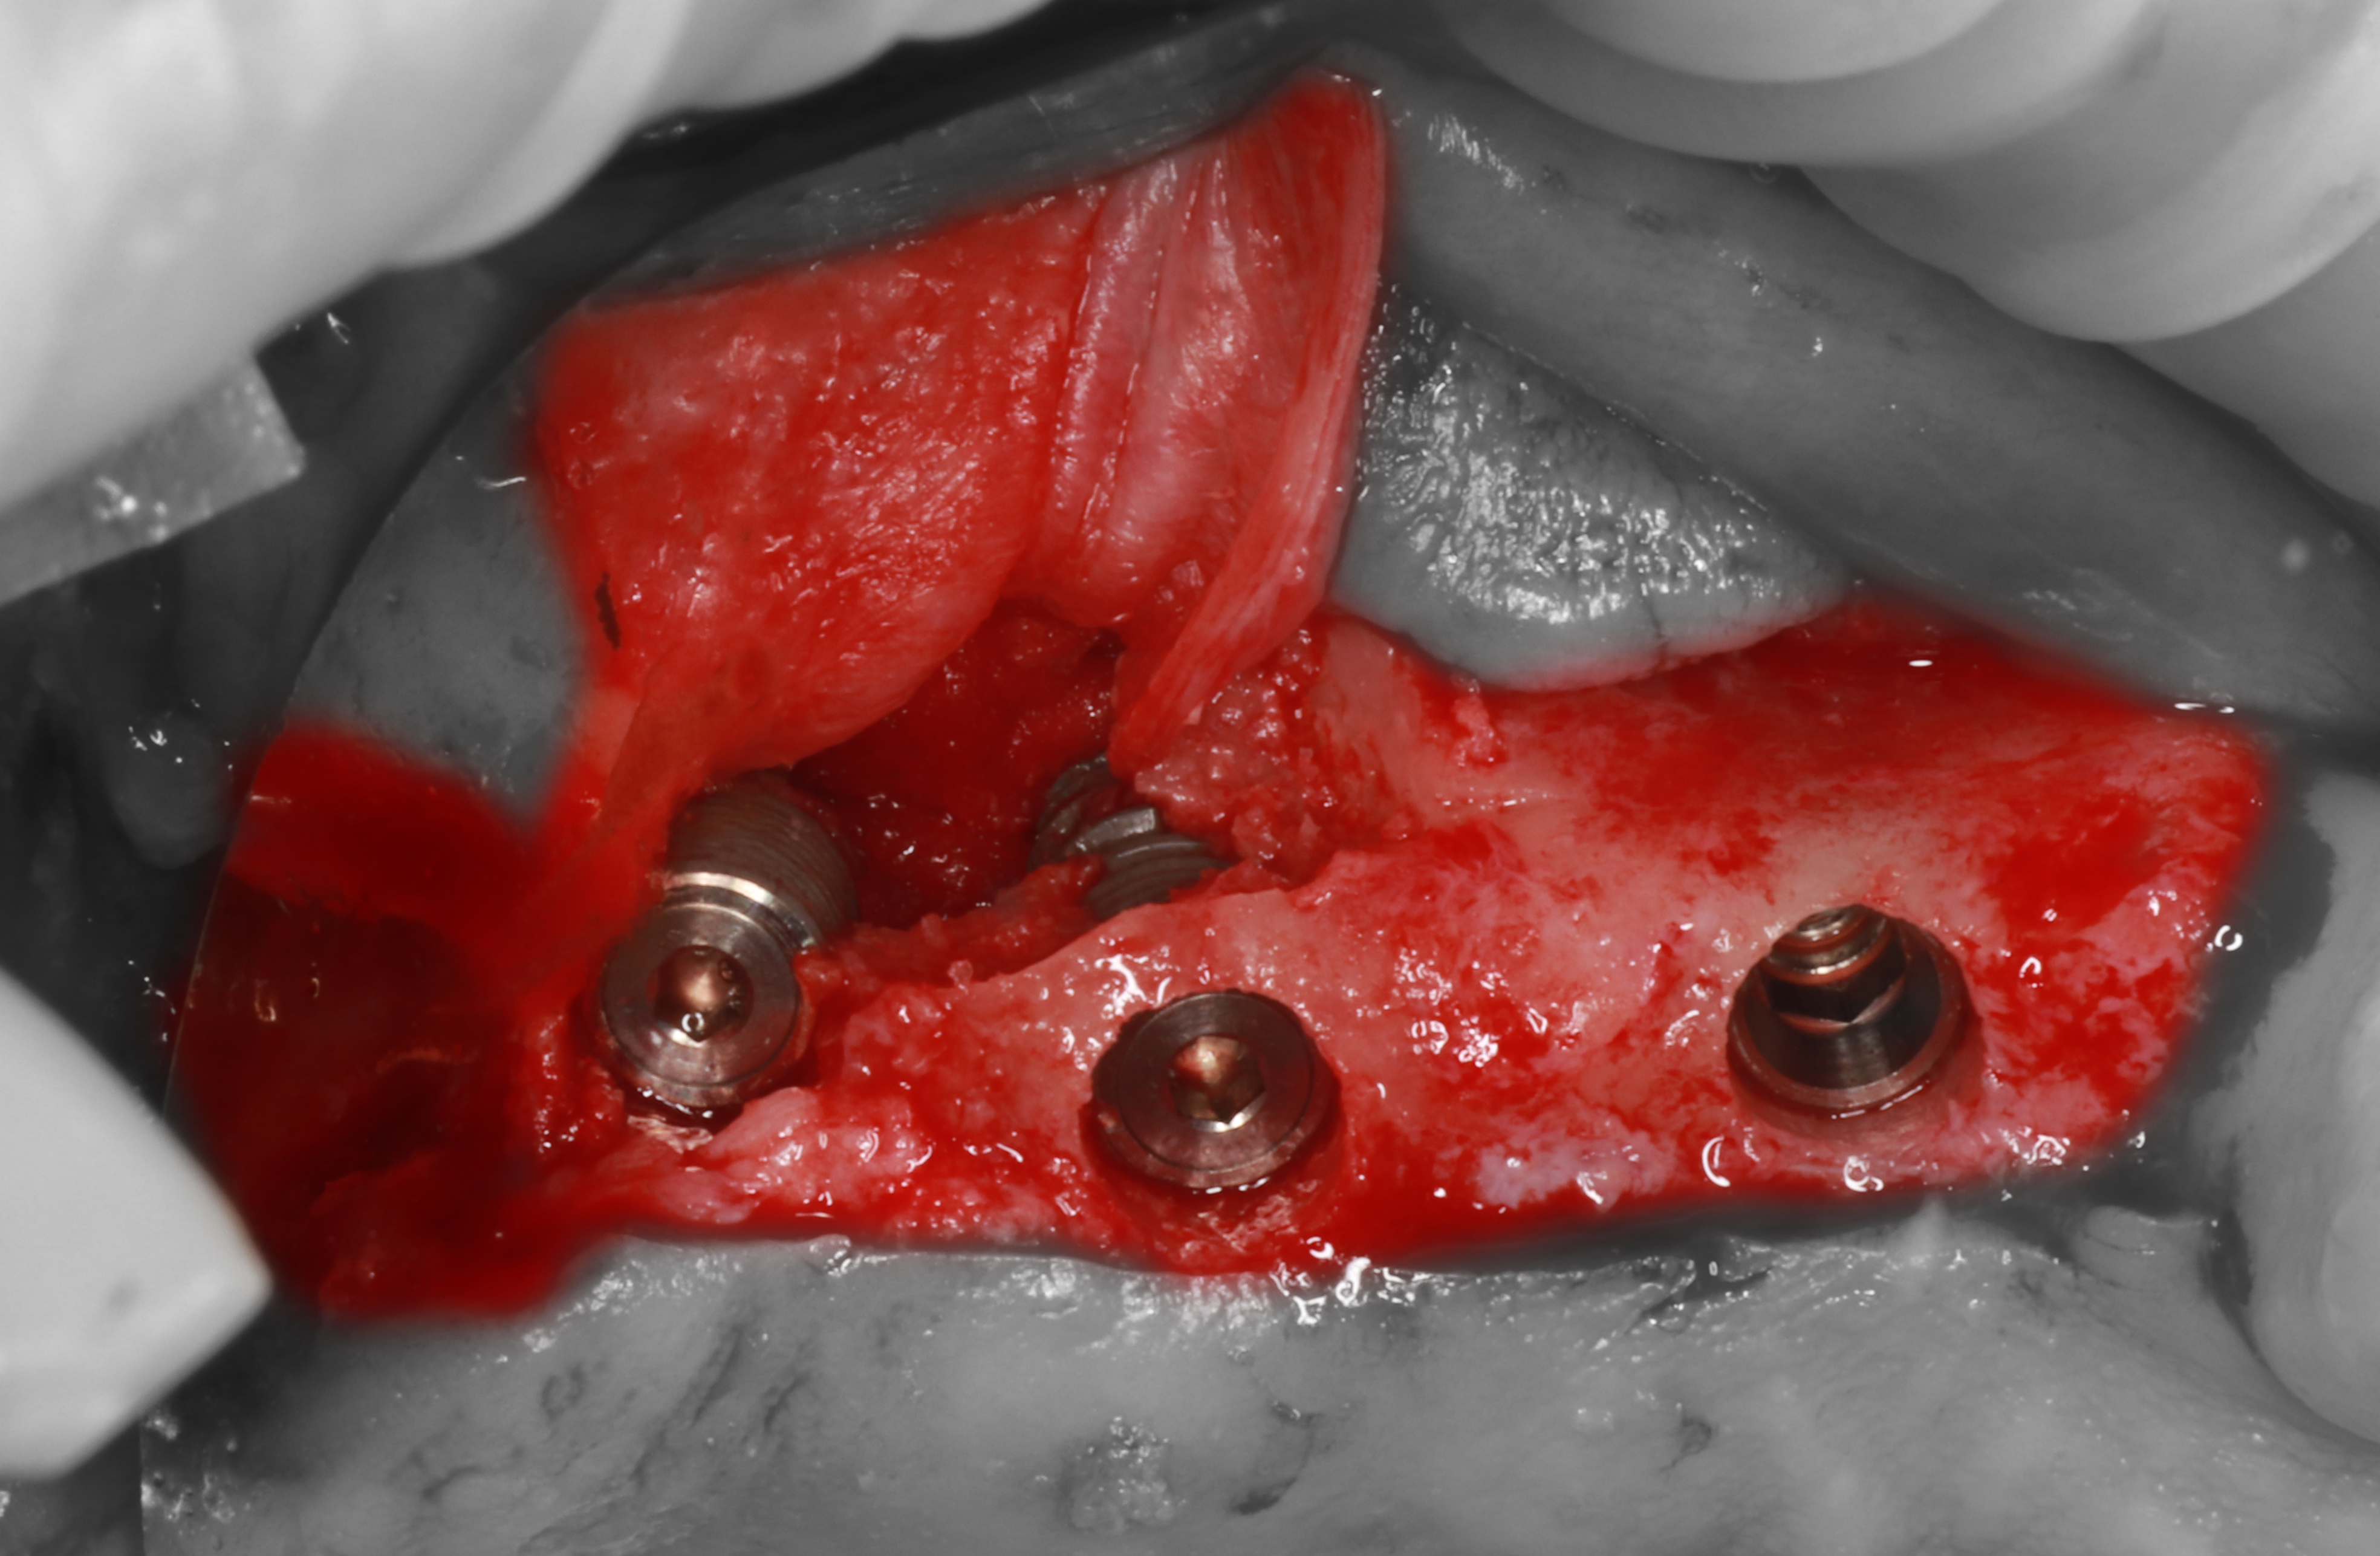

6) Перфорации изолированы с помощью коллагеновой мембраны, установлены имплантаты ICX.

8) Отломавшийся фрагмент костной ткани возвращен на место и фиксирован с помощью пина.